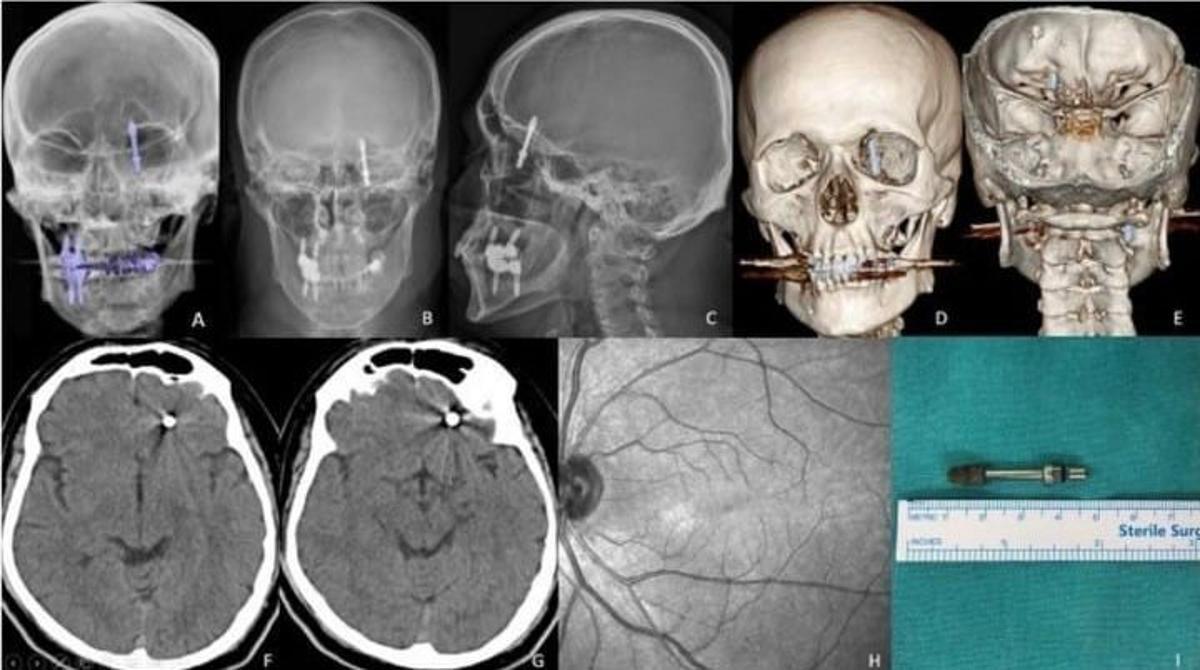

Baygınlık geçiren Yılmaz, kliniğin kendi aracıyla hastaneye kaldırıldı. Tomografi çekiminde vidanın beynine kadar ilerlediği ortaya çıktı. Acil ameliyata alınan talihsiz adam, saatler süren operasyonla ölümden döndü.

Adli tıp raporunun dosyaya eklenmediğini söyleyen Yılmaz, "Beynime implant saplandı ama kimse sorumluluk almıyor. Başhekime kadar gittim, hâlâ bir muhatap bulamadım" diyerek yaşadığı çaresizliği anlattı.